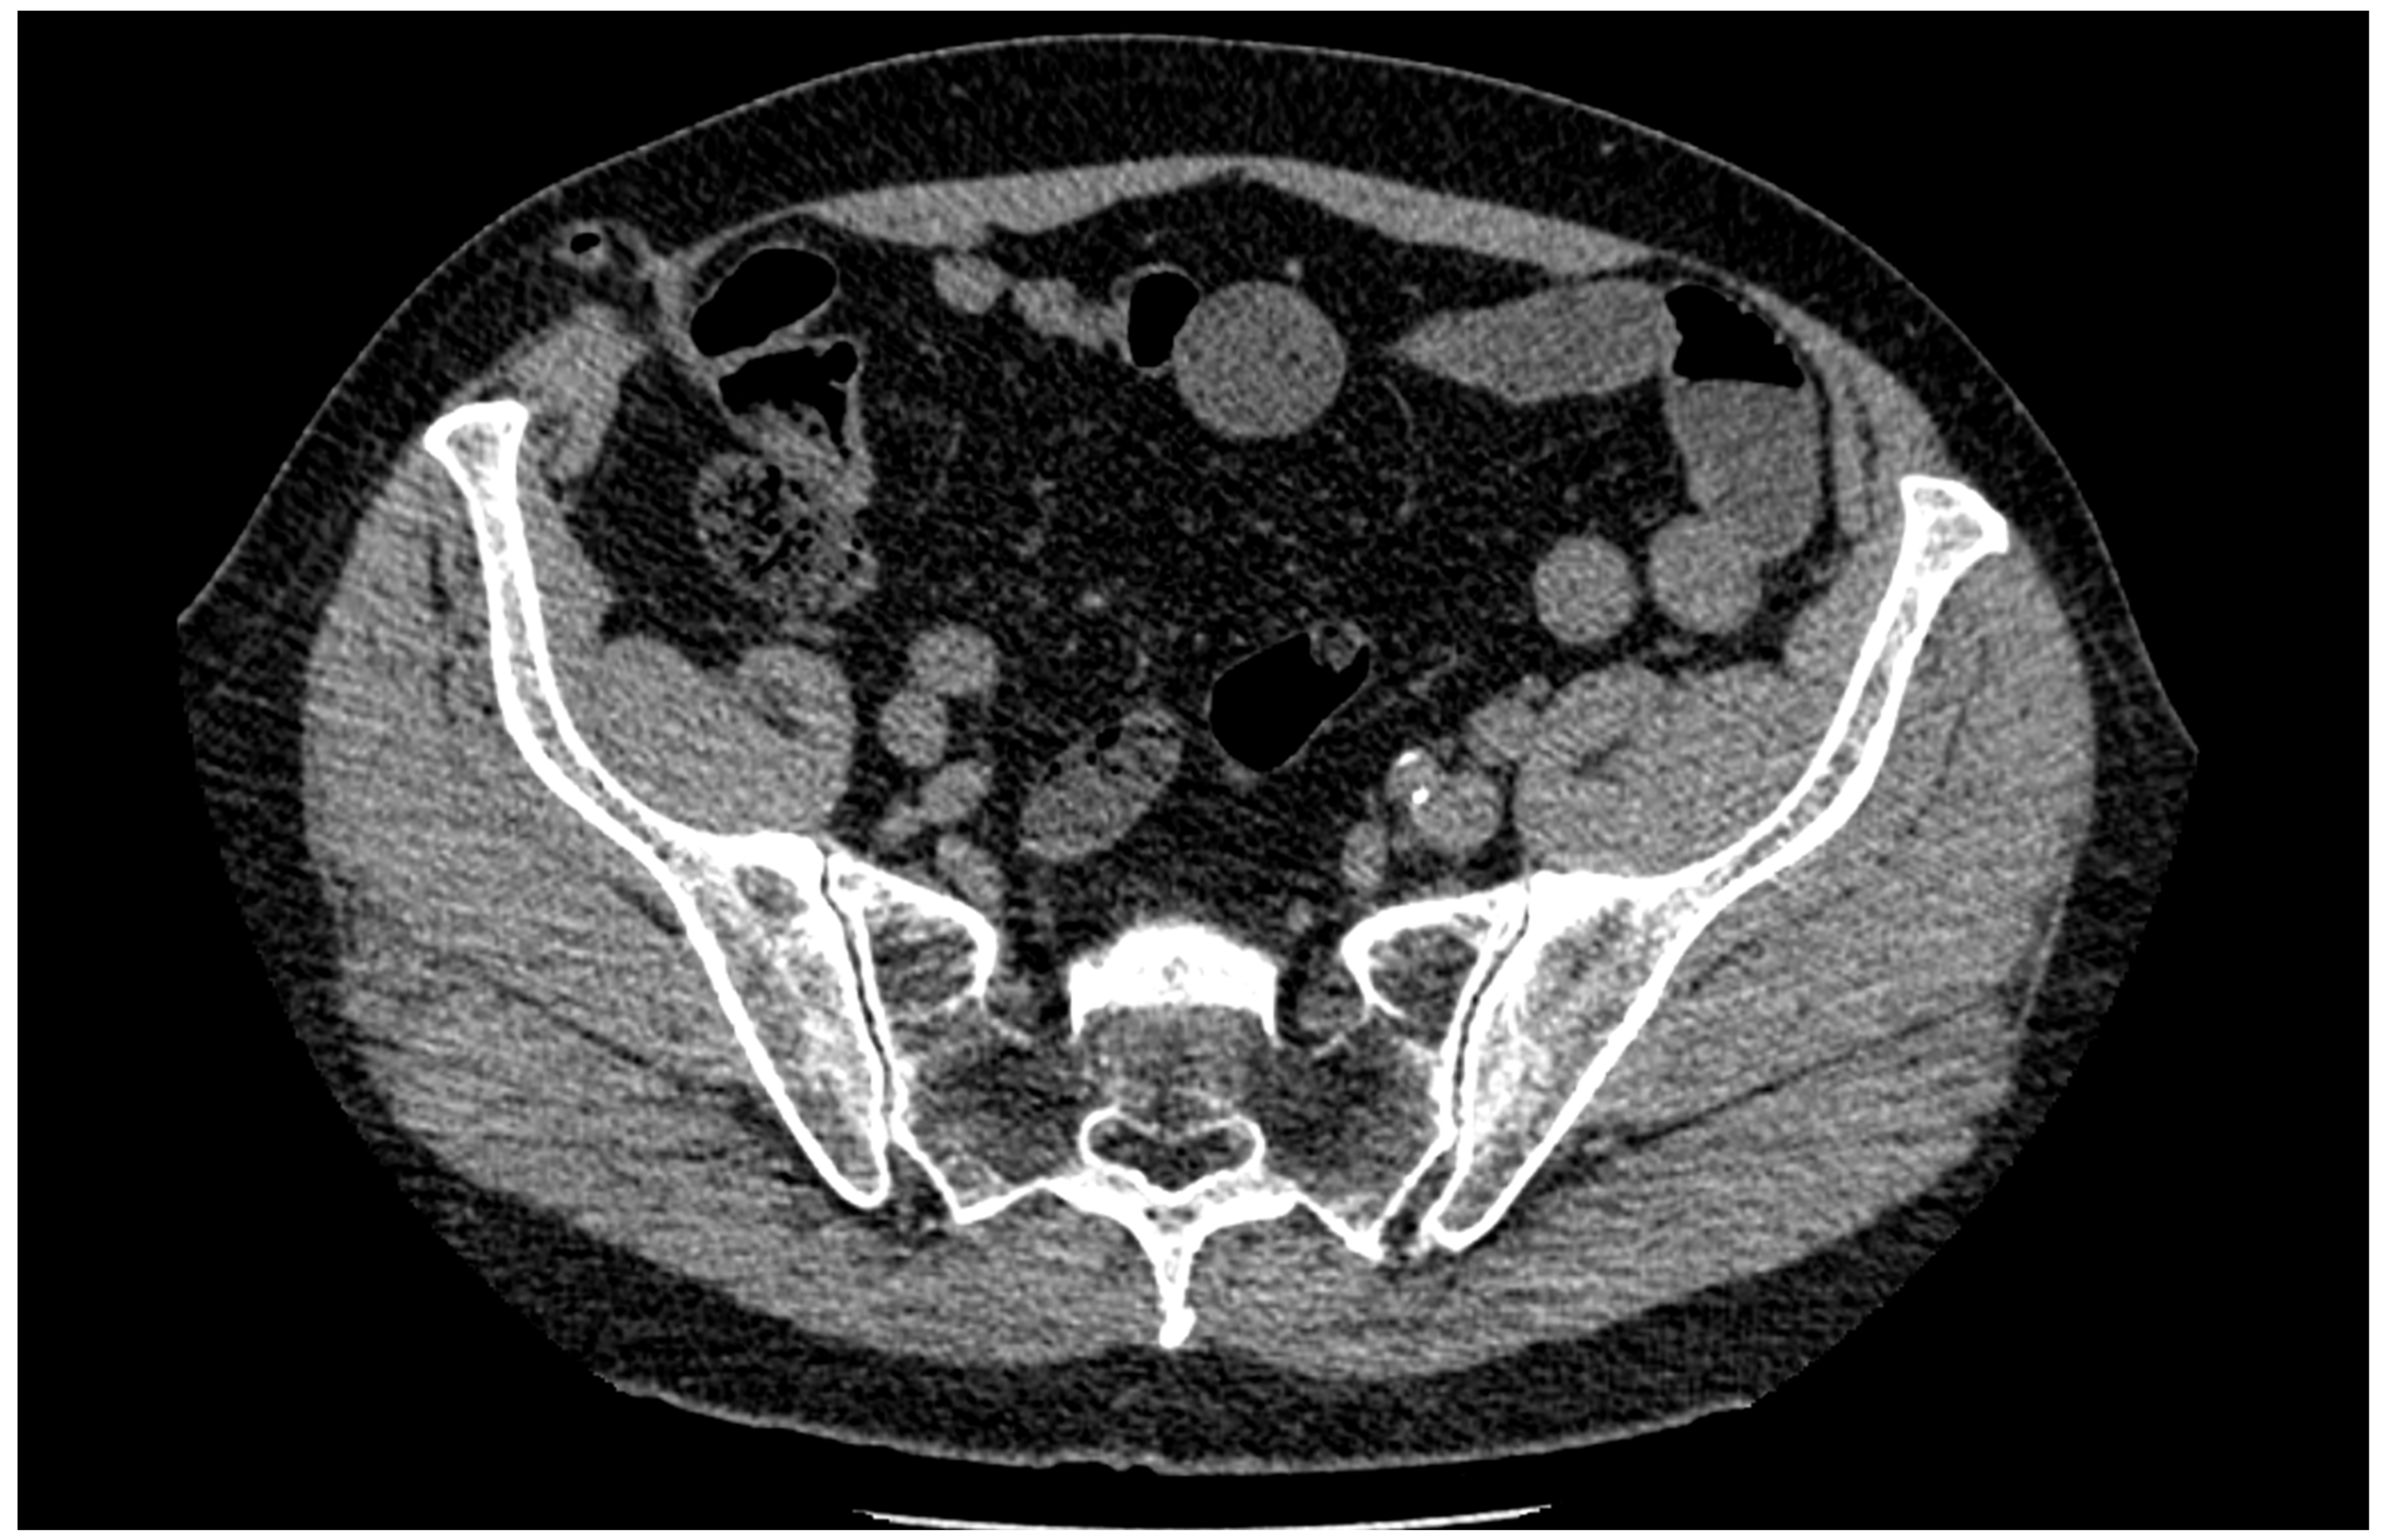

2. Case Report